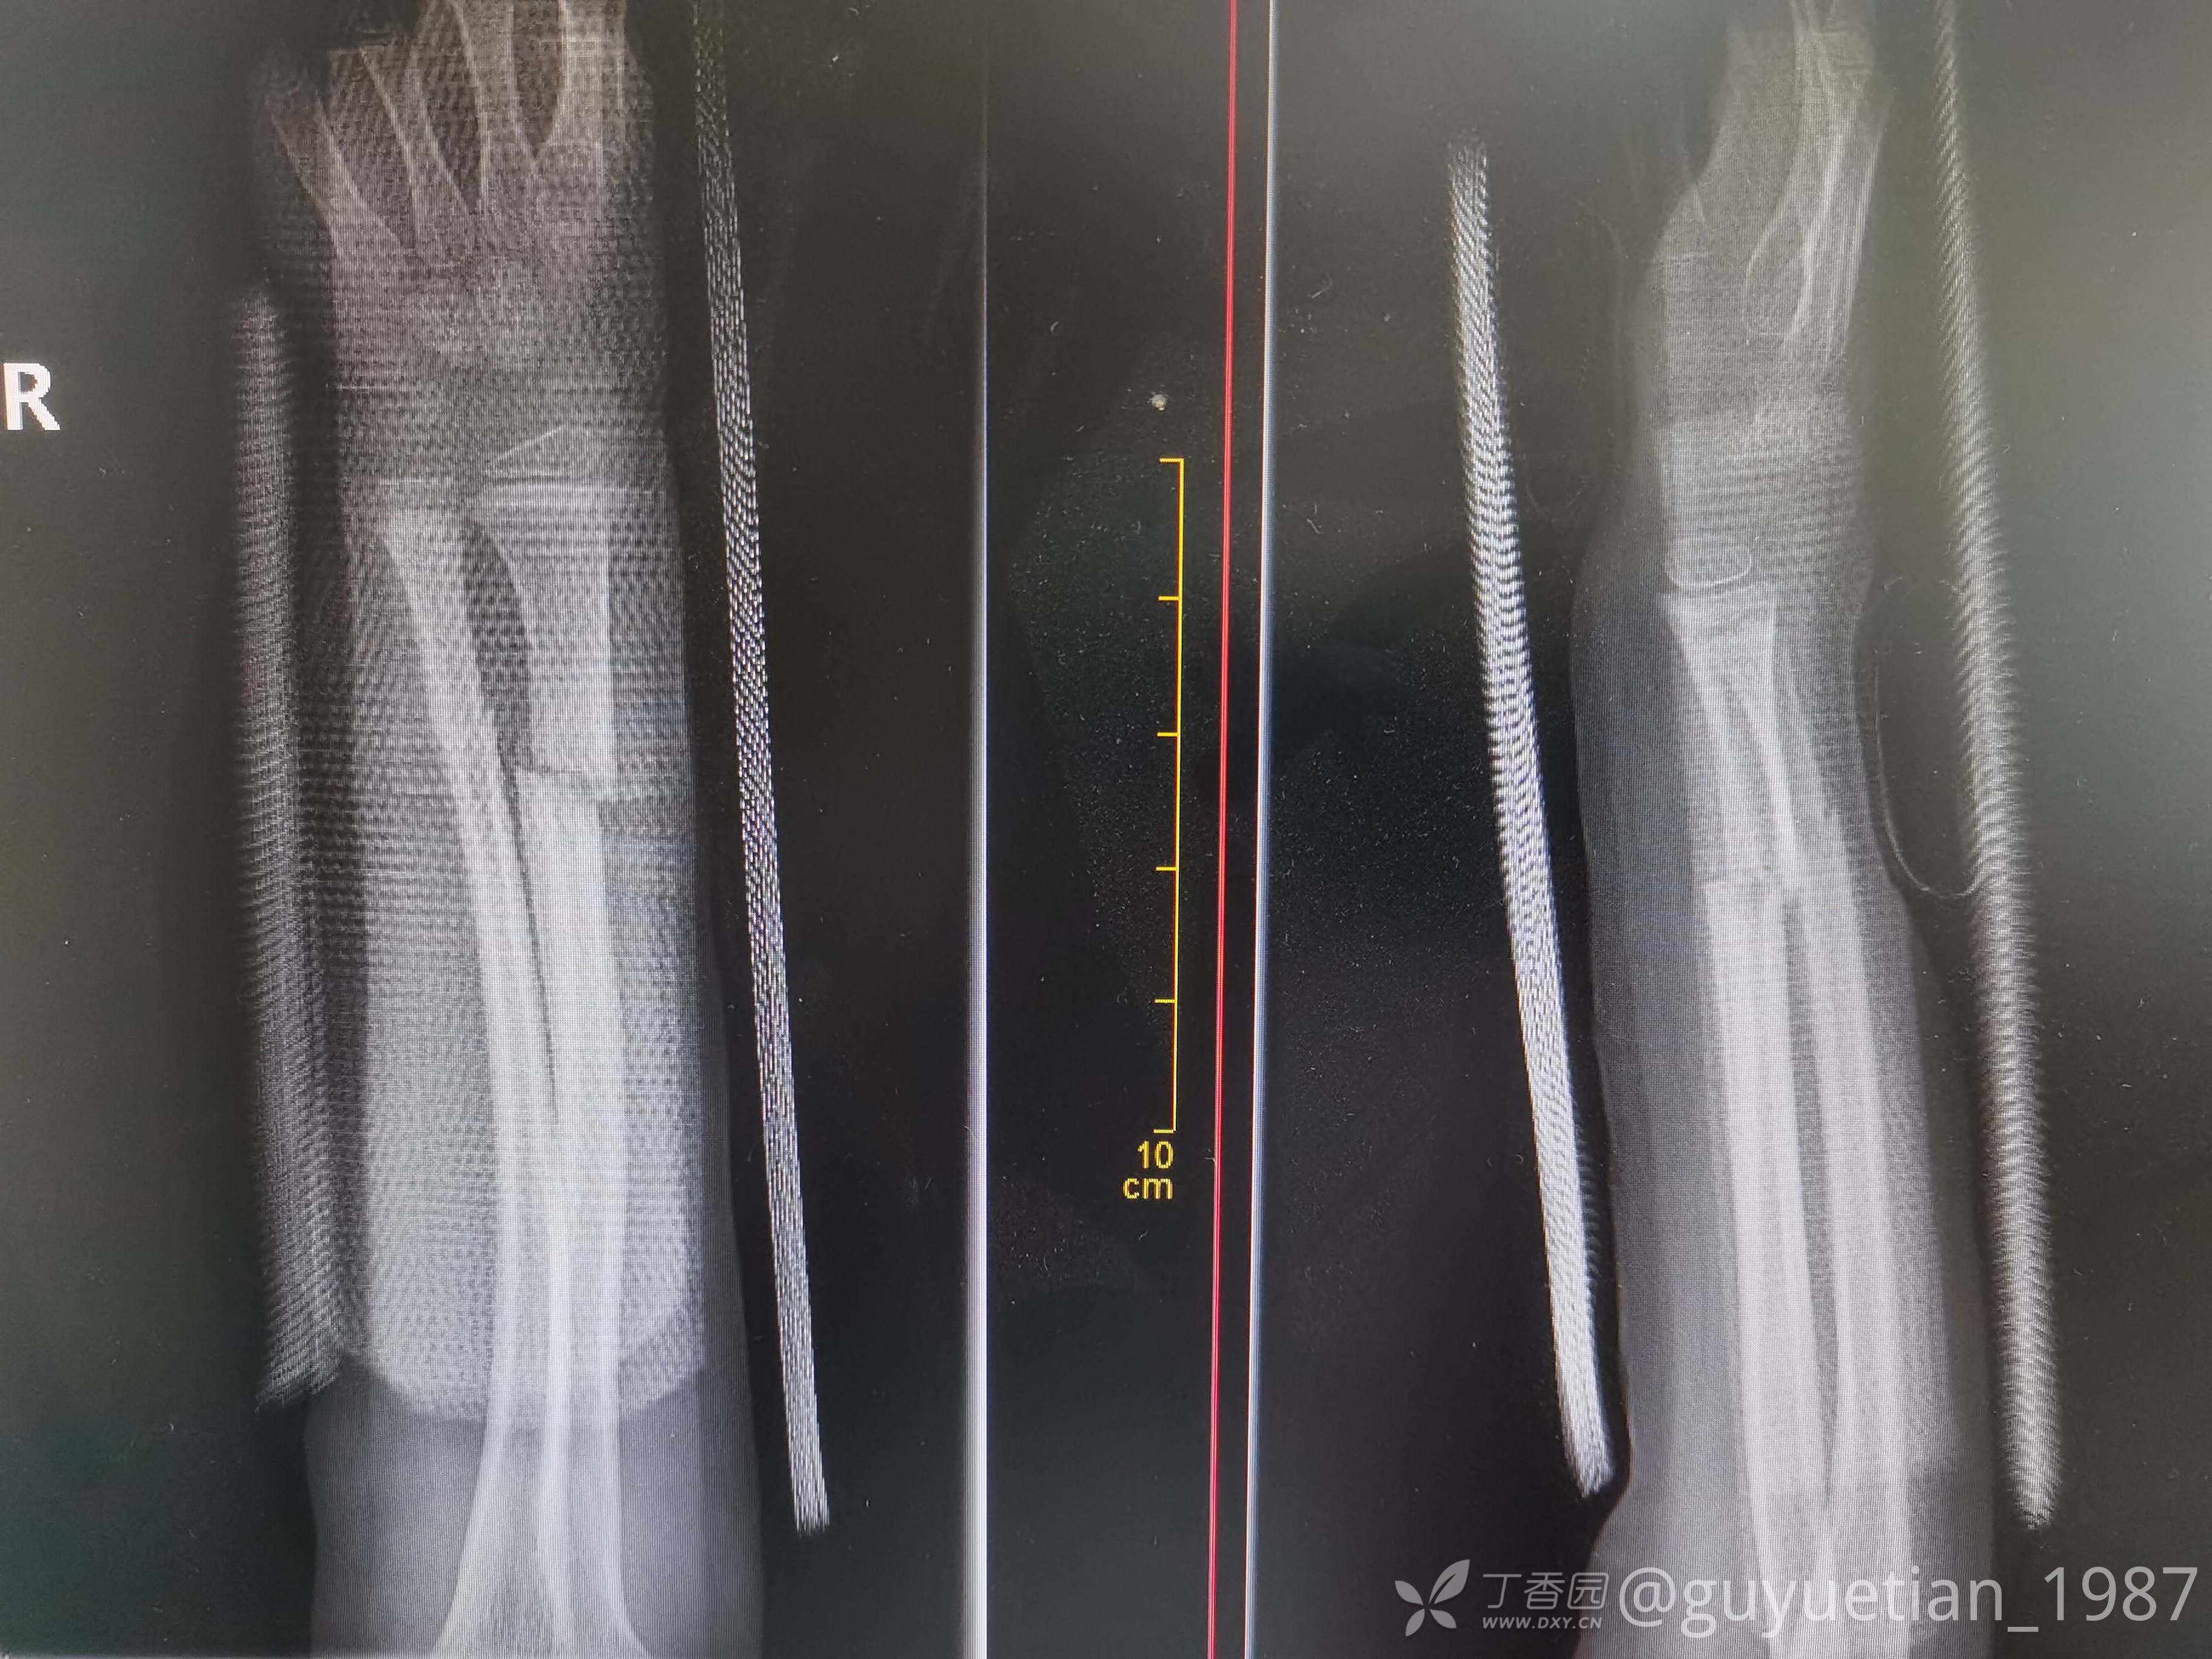

2周后复诊,出现骨痂

3周后,明显看到骨痂,开始塑形。

5周后复诊,解除夹板固定。塑形可以,外观正常。